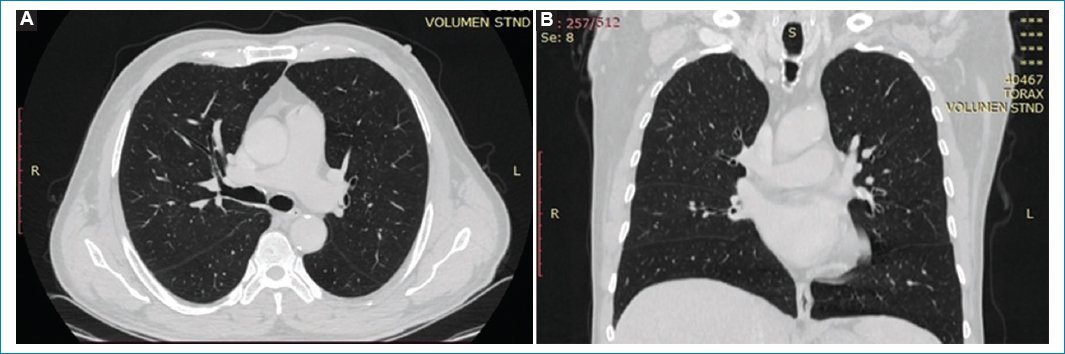

La TC de tórax actual demuestra infiltrados reticulares en ambos parénquimas pulmonares, acompañado de múltiples pequeñas imágenes quísticas de disposición subpleural conformando “patrón en panal de abejas” con predominio de ambos lóbulos inferiores. Se acompaña de bronquiectasias cilíndricas en ambos parénquimas, así como también infiltrado intersticial en vidrio esmerilado, siendo más evidente en las bases. Estos hallazgos se interpretaron como neumonía intersticial usual, lo cual no se observaba en estudios previos (Figs. 2 y 3).

Figura 2. (A y B) TC corte axial en ventana para evaluar parénquima pulmonar, “patrón en panal de abejas” en ambos lóbulos inferiores. Se acompaña de bronquiectasias cilíndricas en ambos parénquimas.